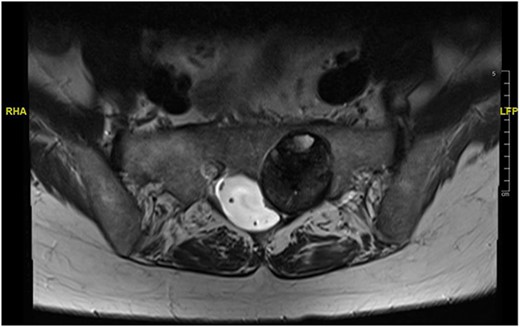

Reviews in July 2019 (with an MRI scan in December 2019) and December 2020 confirmed no neurological deterioration but some increased back and leg pain when standing for some time. A repeat MRI scan confirmed an increase in the size of the lesion (Figs 1 and 2). A biopsy was arranged with a plan for a follow-up surgery. Results of the CT-guided biopsy indicated a diagnosis of metastatic malignant melanoma. Discussions with the patient did not localise any skin lesion responsible for the metastatic deposit, an F18-fluorodeoxyglucose positron emission tomography (18F-FDG PET/CT) scan and a conventional computed axial tomography (CT) scan was organised (April 2021), which revealed sacral destruction and no other deposits in the chest, abdomen and pelvis (Figs 3 and 4). Our patient had a reported SUV of 3.6, indicating a malignant lesion that was then confirmed operatively.

MS comprises <1% of primary peripheral sheath tumours. The most common sites are cervical and upper thoracic spinal nerves with 30–40 years being the most common age group of occurrences [1, 3, 9]. The MRI characteristics of high signal on T1WI and low signal on T2WI with homogenous enhancement with contrast are well known. Our patient was in an older age group during presentation and had no skin deposits. Whereas a diagnosis was made on biopsy, it is also possible to use the FDG uptake on PET/CT imaging to determine the benign or malignant nature of the tumour [1]. The standardised uptake value (SUV) is a simple way of determining activity in PET imaging, most commonly in FDG imaging, and can predict the histologic response [10, 11]. It is used to measure response of cancers to treatment and considered a semi-quantitative value as it is vulnerable to other sources of variabilities [10, 11]. Hamada et al. set the cut-off point to 3.0 for distinguishing benign and malignant lesions [12]. Whereas there is an overlap in the SUV cut-off point amongst various authors, there is also a wide variation between them [13, 14]. Ahmed et al. reported 0.33–3.7, whereas Aoki et al. reported 1.75 ± 0.84 [14, 15]. However, Aoki et al., in another paper, reported a wider range of 0.7–2.84 [13]. Our patient had a reported SUV of 3.6, indicating a malignant lesion that was then confirmed operatively.